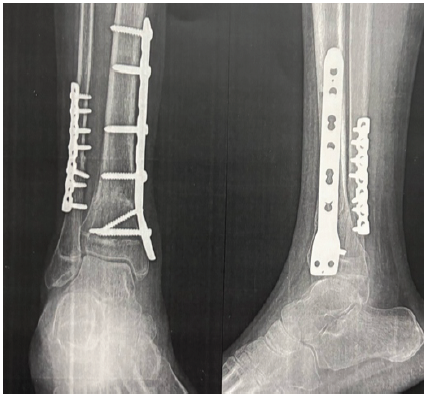

A 16-year-old male presented with complaints of persistent deformity of the right great toe and other toes, associated with discomfort during walking and difficulty wearing closed footwear. He had allegedly sustained a closed distal tibia and fibula fracture 3 years prior, which was managed with open reduction and internal fixation. The patient noticed the onset of great toe deformity approximately 3 weeks postoperatively, with increasing severity over time. Despite conservative measures, including physiotherapy, the deformity persisted and began to interfere with daily activities. On clinical examination, there was a visible dynamic flexion deformity of the right great toe that accentuated with active or passive dorsiflexion of the ankle and resolved on plantarflexion. The other toes also had dynamic flexion. The limb was neurovascularly intact. Radiographs of the leg and foot showed well-healed fractures with intact implants (Fig. 1 and 2).

Figure 2: Pre-operative X-ray.